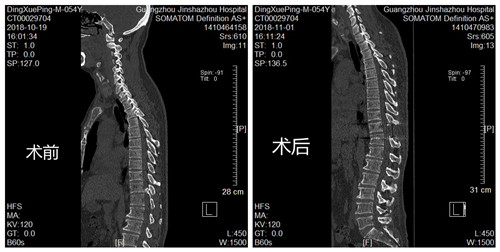

丁叔术前术后CT对比照

胸椎内固定术后CT

经过详细地询问病史和全面的体格检查,CT提示黄韧带骨化,相应胸椎管狭窄。丁叔就是由于胸椎黄韧带骨化,压迫胸髓引起左下肢痉挛性瘫痪,左下肢僵硬、活动不便、偏瘫步态,严重影响日常生活。

骨科中心郑主任精心为丁叔制定了详细的手术方案,做好了充分的术前准备,降低了手术风险,使得丁叔的手术顺利完成,术后左下肢肌张力明显下降,肢体活动灵活、行走步态明显改善,临床治疗效果佳,经过几天的康复锻炼和功能训练,现在丁叔已康复出院、平安归家。